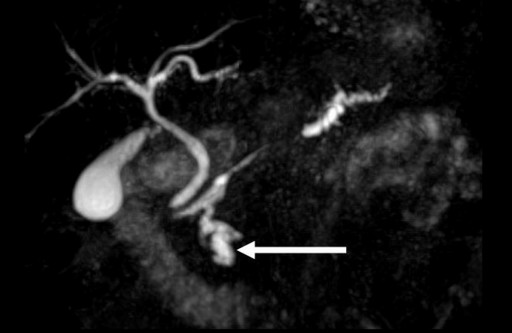

A 56-year-old man was admitted to our hospital for recurrent pancreatitis. Noteworthy aspects of his medical history included alcohol and tobacco consumption, an ischemic stroke related to right carotid aneurysmal rupture and hypertension. Following the stroke, he suffered from left hemiplegia and epilepsy. Although he no longer consumed alcohol, he had been treated for two episodes of acute pancreatitis during the previous year. He complained of epigastric pain at the time of the consultation (his medical treatment included 40 mg of morphine orally per day) and, upon physical examination, he was found to have left hemiplegia without jaundice, fever or weight loss. Abdominal palpation did not detect any abnormal mass and laboratory examination revealed no hyper-leucocytosis or anemia. Hepatic and pancreatic enzymes were slightly increased (ALT: 52 IU/L, reference range: 0-41 IU/L; AST: 43 IU/L; reference range: 0-38 IU/L; lipase: 264 IU/L, reference range: 114-286 IU/L; amylase: 100 IU/L; reference range: 25-115 IU/L), but there was no biological cholestasis. An abdominal CT scan showed a polycystic lesion, 26 mm in diameter, located in the uncus. This lesion was associated with a concurrent stenosis of the isthmic pancreatic duct which resulted in a distal dilation (Figure 1). Following an endoscopic ultrasound and MRI, the cystic lesion was characterized as a typical branch-type IPMT and the ductal dilation was attributed to chronic pancreatitis (Figure 2). The final diagnosis was, therefore, of chronic pancreatitis related to an IPMT of the uncus. A surgical resection of this IPMT was carried out. A Whipple procedure was then performed with extemporaneous histological analysis of the pancreatic cut edge, revealing the presence of malignant cells. In view of these histological findings, the pancreatic incision was shifted 3 cm to the left of the pancreatic isthmus, revealing no malignant cells upon extemporaneous histological analysis. Definitive histological analysis confirmed the diagnosis of an IPMT in the uncinate process (Figure 3) as well as a concurrent adenocarcinoma, 1 cm in diameter, located 2 cm from the primary IPMT, in the isthmus (Figure 4). The patient had an uneventful postoperative course and was discharged from the hospital 15 days following surgery. The patient subsequently underwent adjuvant chemotherapy. He is alive without recurrence 7 months following the surgery. Upon postoperative review of the original CT scan, we noted that the stenosis which was initially attributed to chronic pancreatitis was, instead, due to a lesion that we had not originally identified and which corresponded to the concomitant adenocarcinoma.

Figure 2. Cholangio-magnetic resonance image: 26 mm branch type IPMT located in the uncus (white arrow) concomitant with a Wirsung dilation of the pancreatic body. |